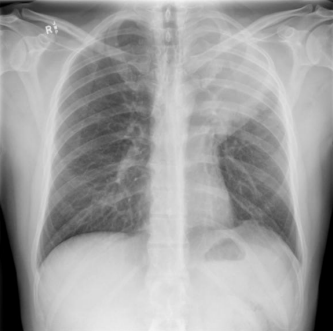

Homem de 30 anos, previamente hígido, farmacêutico, é atendido em ambulatório devido à queixa de tosse seca de mais de 6 meses de evolução. Buscou atendimento, pois vem tendo episódios de febre durante a noite, acompanhados de sudorese profusa, que cessam ao uso de dipirona. Durante anamnese, nega escarro produtivo, hemoptise, dor torácica ou dispneia, mas refere perda de peso discreta no período. No exame físico, evidencia-se adenomegalia de cerva de 2 centímetros em cadeia cervical anterior esquerda, pouco endurecida, aderida a planos profundos, sem sinais flogísticos, além de abaulamento discreto em fossa supraclavicular ipsilateral. Ausculta pulmonar com murmúrio vesicular reduzido, percussão com submacicez e frêmito toracovocal aumentado em ápice esquerdo, além de sibilos discretos em hemitórax esquerdo. Realizou a radiografia abaixo.

Com base no caso acima, a hipótese diagnóstica mais provável para o paciente é